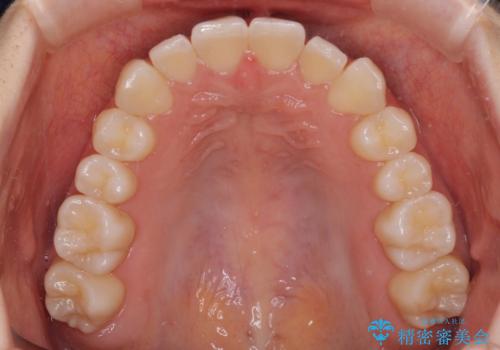

前歯のクロスバイト インビザラインによる矯正治療

- 前歯のクロスバイトを気にして来院された患者様です。

短期間での治療を希望され、ワイヤー装置とインビザラインとで悩んでいましたが、自己管理を徹底すると言うことでインビザラインによる矯正治療を行うこととしました。

しっかりとインビザラインの装着時間を守っていただいたので、1年弱で矯正治療を終えることができました。